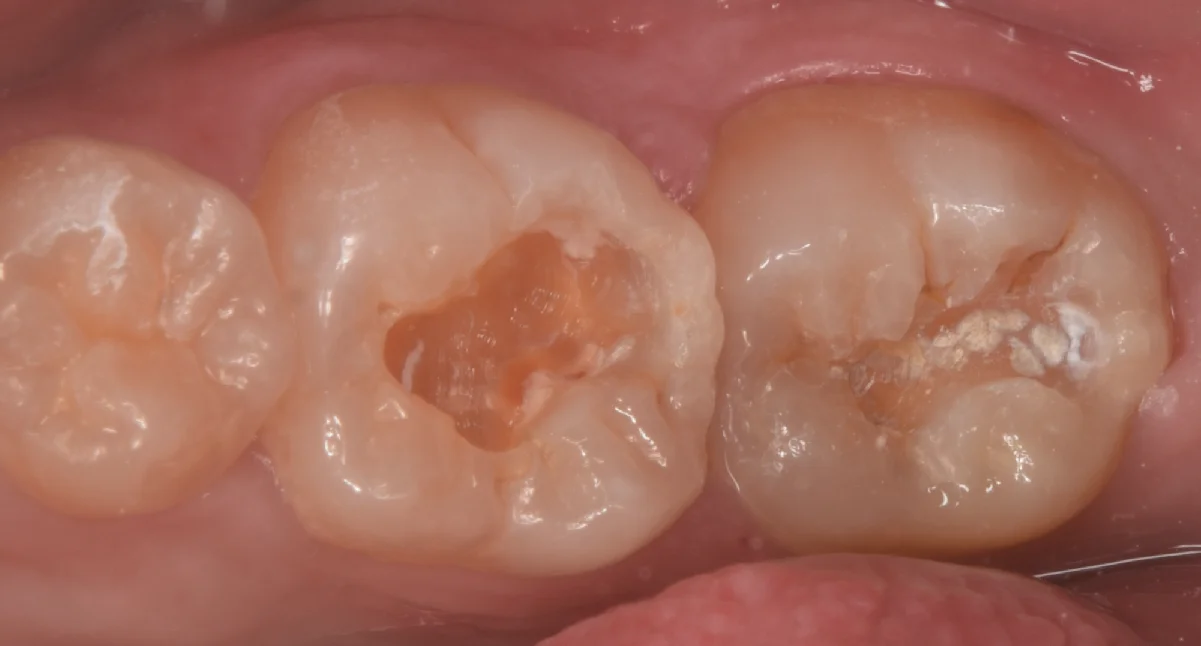

古い詰め物だけ除去して虫歯が見えやすい状態にしたのがこちらになります。

真ん中にある歯が実は相当な虫歯のサイズでした。

色は黒っぽくないので虫歯っぽさがないですが、じつはこんな感じで色が薄い虫歯が進行速度が早く、重症化しやすい上に見た目だとわかりづらいので歯科医師としては結構嫌な虫歯のタイプになります。

右側の歯も同様にそこまで深くないように見えます。